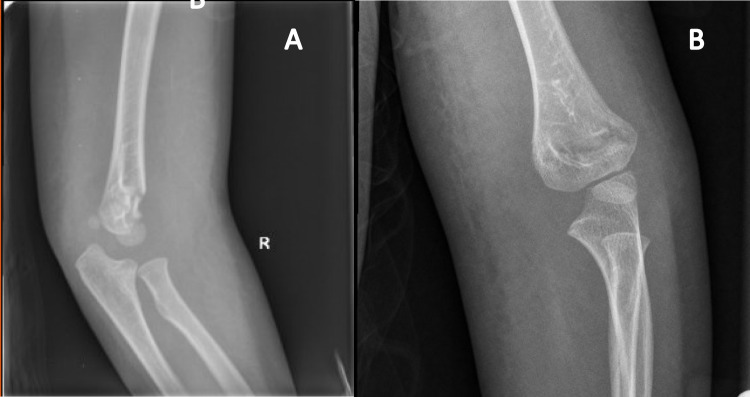

综述目的:本综述旨在全面分析小儿Gartland II型骨折的非手术治疗。最近发现:肱骨髁上骨折(SCF)是儿童人群中最常见的创伤性骨折之一,其特征是肱骨远端内侧柱和外侧柱之间的横向骨折。早期研究强烈反对将闭合复位和铸造作为Gartland II型骨折可接受的治疗方式,因为早期病例系列显示并发症发生率高;然而,最近的研究表明效果更好。Gartland II型髁上骨折的最佳治疗方法尚未完全阐明。本文综述了Gartland II型肱骨髁上骨折非手术治疗的适应症、并发症和结果。此外,它表明需要进一步的研究来指导管理这种情况。

Recent findings: Supracondylar humeral fractures (SCF) are one of the most common traumatic fractures in pediatric populations, characterized as transverse fractures at the distal humerus between the medial and lateral columns. Early studies strongly opposed closed reduction and casting as an acceptable treatment modality for Gartland type II fractures as an early case series showed high rates of complications; however, more recent studies have suggested better outcomes. The optimal management of Gartland Type II supracondylar fractures has yet to be fully elucidated. This review highlights the indications, complications, and outcomes of nonoperative Gartland Type II supracondylar humeral fracture management. Additionally, it demonstrates the need for further research to inform guidelines on managing this condition.